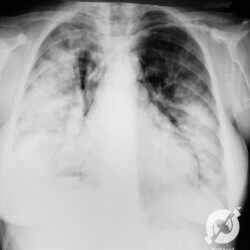

Aumento do volume cardíaco, lesões intersticiais reticulares e obliteração do seio costofrênico direito.